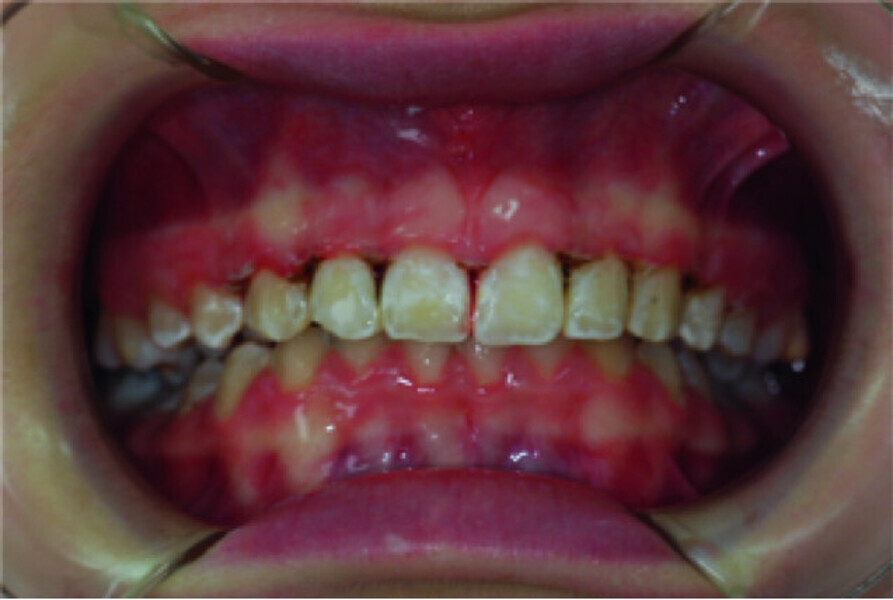

Use of diode laser in the treatment of gingival enlargement during orthodontic treatment